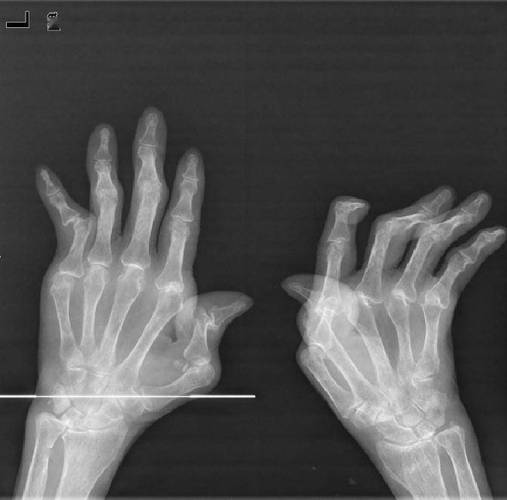

X光片主要观察的是骨骼和关节的结构变化,在类风湿关节炎中,这些变化是由于长期的滑膜炎症侵蚀了软骨和骨骼导致的。

- 关节间隙狭窄: 这是最关键的X光表现之一,正常软骨在X光下是看不见的,所以关节间隙其实是软骨的厚度,当类风湿关节炎的炎症侵蚀掉软骨后,X光片上就能看到关节之间的空隙变窄了。

- 骨侵蚀: 这是另一个最具诊断价值的特征,炎症的增厚滑膜(血管翳)会像“癌细胞”一样,从关节边缘开始侵蚀骨骼,在X光片上形成边缘清晰的、小洞样的骨质缺损,常见于手指、手腕的掌骨头和指骨的基底部。

- 关节畸形: 当软骨和骨骼被严重破坏,关节周围的韧带和肌腱也因炎症而松弛或断裂时,关节就会失去正常的对位关系,导致畸形,例如手指的“天鹅颈”样畸形、“钮扣花”样畸形,手腕的尺偏畸形等。

- 骨性强直: 在极晚期,严重的骨侵蚀和修复反应可能导致关节面完全融合,活动完全丧失,这在X光片上表现为关节间隙消失,骨头长在了一起,类风湿关节炎更常导致的是纤维性强直(活动受限但X光上没长死),骨性强直相对少见。